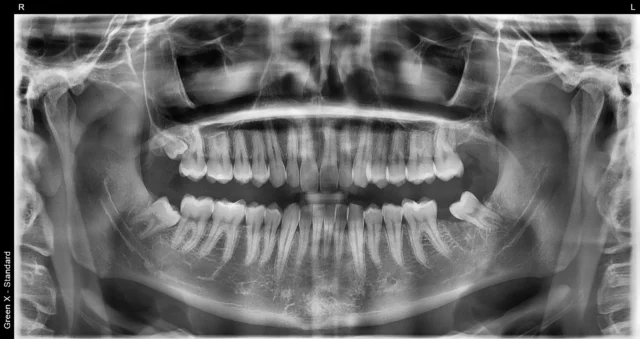

Diagnostyka: RTG i tomografia CBCT

Skuteczność leczenia zależy od precyzyjnej diagnostyki. W Pro EndoDentica wykonujemy:

- RTG zęba oraz pantomogram do oceny ogólnej.

- CBCT 3D do analizy pęknięć, perforacji, przebiegu kanałów, ubytku kości i relacji do struktur anatomicznych.

Na tej podstawie omawiamy scenariusze: hemisekcję połączoną z leczeniem kanałowym pozostałego korzenia, tylko hemisekcję z odbudową protetyczną lub alternatywne procedury.